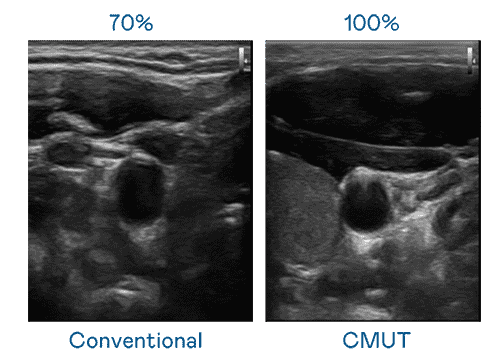

CMUT 技术是一种用电容式微机电元件来产生超音波讯号的技术。。。与传统 PZT 压电式技术相比,,,CMUT 频宽增加 30%,,更宽频的超音波讯号让影像解析度大幅提升,,,,是实现高影像品质医疗超音波扫描、、、促进精准医疗发展的关键技术。。。。

大频宽带来超清晰影像

超音波影像的解析度高低,,,首先取决于探头能发出的讯号频宽。。。。赏金国际 CMUT 可提供高清晰的超音波讯号,,,,提供高频宽、、高灵敏度、、、、影像纹理细节更高的超音波影像,,协助医护人员缩短影像判读时间及利用精准的医疗影像进行诊断。。。。